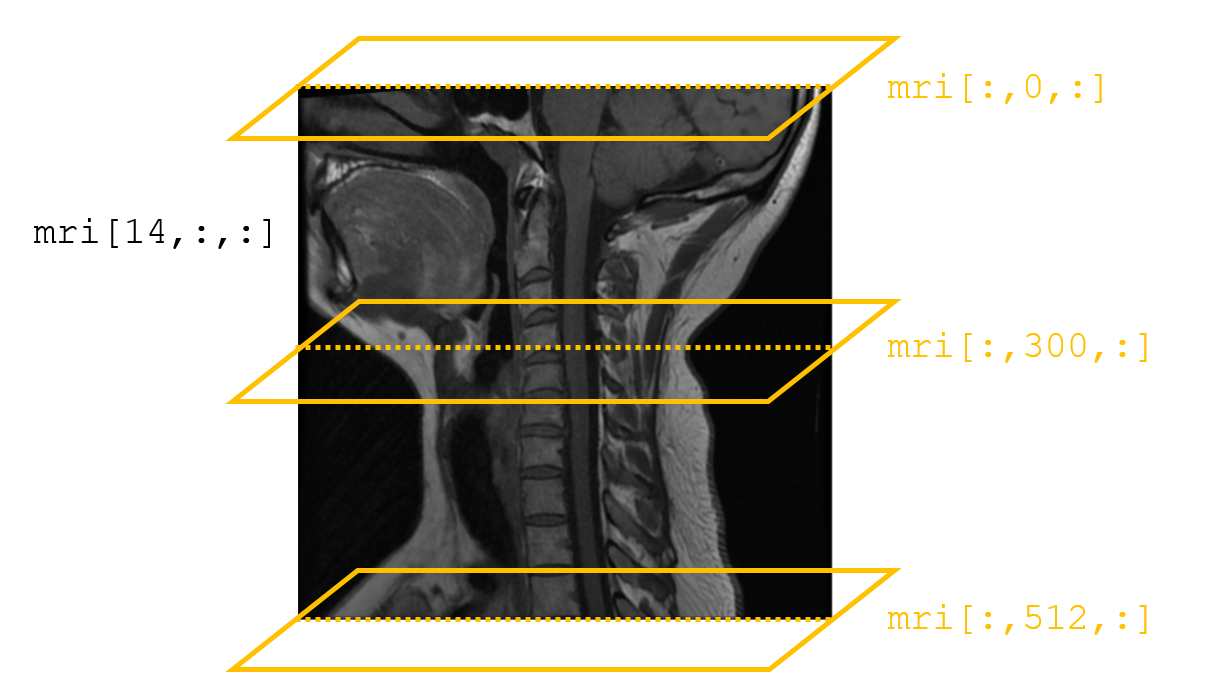

To illustrate, consider the case of an MRI. While we’ve all seen two-dimensional MRI images, but a real MRI scan consists of a series of these two-dimensional slices stacked on top of one another to form a three-dimensional picture of patients. And this data can very naturally be represented in a three-dimensional numpy array!

As we can see, this MRI is represented by a three-dimensional array. More specifically, it consists of 15 stacked images, each of which is 512 x 512 pixels. And since this is just a set of stacked images, we can easily pull out one of these slices and visualize it:

Finally, because this data is three-dimensional, we also have the option of cutting our own slices along a different axis. In the images above, we’ve specified a specific value for the first dimension of our array and plotted the second and third dimensions along the x and y-axes of our image. This has given us vertical slices of the patient’s neck.

But if, instead, we fix a value of the second dimension, we can actually get a horizontal slice of the patient’s neck. Now, because we only have 15 slices along the first dimension of our array, the resolution along this axis is not nearly as good (a full MRI study includes taking detailed slices along all axes, and CT scans can be used to generate volumetric data with consistent resolution along all axes), but it does illustrate how working with volumetric data allows us to really explore three-dimensional objects:

If that feels a little abstract, consider this illustration of what we just did. We start with our image that shows the patient’s full skull and neck from the side (mri[14, :, :]), then overlay it with the horizontal slices we pulled above: